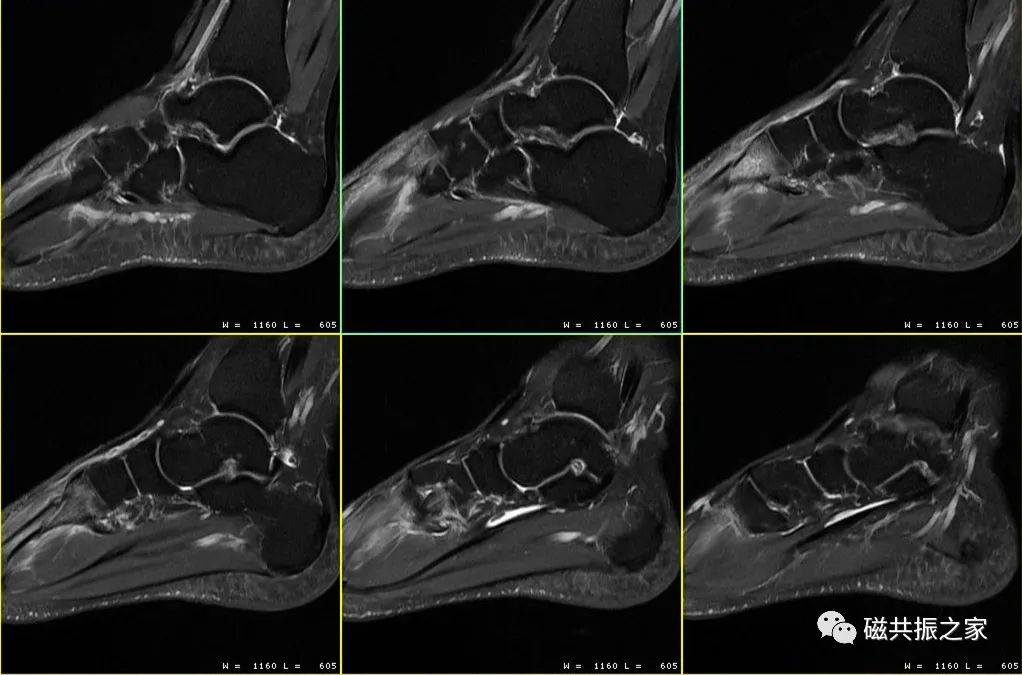

除此之外,摆位时还需选择合理的线圈,抓住你需要观察的重点等,在其规范化摆位的基础上做到个性化的摆位。如上图△,对于足踝部的扫描,做好其压脂的均匀性是其难点之一,那么我们在进行该部位扫描时怎样摆位才能获得比较优异的图像。

如图,上1,2幅图像为带宽12.5kHz;下1,2幅图像为带宽31.2kHz,(GE机型);虽然上两幅图像的信噪比比下两幅图像更高,但其分辨率明显不及带宽为31.2kHz的图像。

如图,上1,2,3幅图像的频率编码数为320;下1,2,3幅图像的频率编码数为512;虽然下面三幅图像的扫描体素较上面三幅图像更小,但其分辨率不及上面三幅图像。图像的分辨率并不是由单一参数决定的,在调整参数时应综合考虑时间、信噪比、对比度、伪影等相关因素。